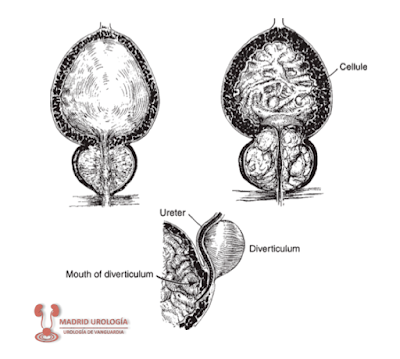

Esquemáticamente.

Izquierda: vejiga y próstata normal. Derecha: HBP generando OSV y alteraciones

en la morfología vesical.